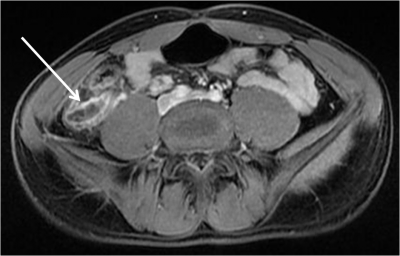

A ultrassonografia abdominal pode ser muito útil para confirmação diagnóstica. Os achados serão de dor à compressão com o aparelho, estrutura tubular de fundo cego, sem peristalse, com diâmetro maior ou igual a 6 mm à compressão com o aparelho, com líquido ao seu redor. A visualização do fecalito e os outros sinais ecográficos praticamente diagnosticam a condição. Muitas vezes a identificação do apêndice pode ser difícil na ultrassonografia, como em pacientes obesos e quando o apêndice é retrocecal, devendo-se realizar outros exames nos casos duvidosos.

A tomografia computadorizada de abdome apresenta valores iguais ou superiores aos da ultrassonografia. O uso desse exame é limitado devido a custo, exposição à radiação e alergia ao contraste. Apresenta boa sensibilidade, pois o apêndice é mais facilmente localizado e características como aumento do seu calibre, inflamação dos tecidos a volta e presença de fecalito na base do apêndice e líquido são altamente sugestivos de apendicite aguda.

Figura 1: imagem de tomografia mostrando apêndce cecal distendido. Figua 2: imagem de tomografia mostrando fecalito na base do apêndice ceal.